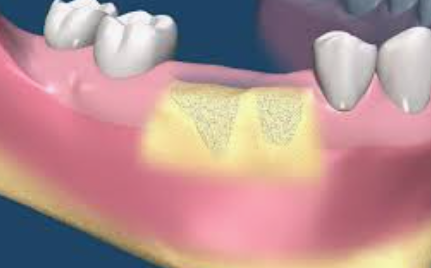

임플란트 뼈이식 혹은 골이식은 뼈 조직을 삽입 (이식)하는 수술입니다. 치과 임플란트의 맥락에서 뼈 이식은 턱뼈의 높이 또는 너비를 증가시켜 임플란트를 위한 안정적인 기반을 제공하는 것을 목표로 하는데요. 이 임플란트 뼈이식 시술은 치주질환, 발치, 외상, 노화 등으로 골소실이 있는 환자에게 필요한 경우가 많습니다.

임플란트는 턱뼈가 임플란트와 융합되는 과정인 안정성과 골유착을 위해 일정량의 뼈가 꼭 필요합니다. 뼈가 부족하면 시간이 지남에 따라 임플란트가 실패할 수 있습니다. 임플란트 뼈이식은 뼈의 양과 질을 향상시켜 임플란트의 수명을 보장함으로써 치과 임플란트 수술의 성공률을 높일 수 있기 때문에 아주 중요합니다.

5. 이식 재료의 배치

추출 혹은 채취한 임플란트 뼈이식 재료는 원하는 위치에 배치됩니다. 어떤 경우에는 이식편을 덮기 위해 특수 막을 사용할 수 있습니다. 이 막은 연조직 및 박테리아가 뼈 이식편으로 침입하는 것을 방지하고 뼈 재생을 도와줍니다.